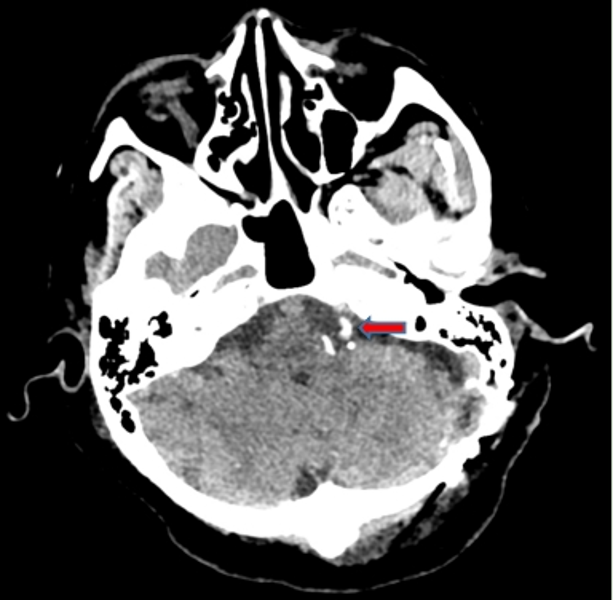

01

图三:术后复查CT(血管垫片位置)